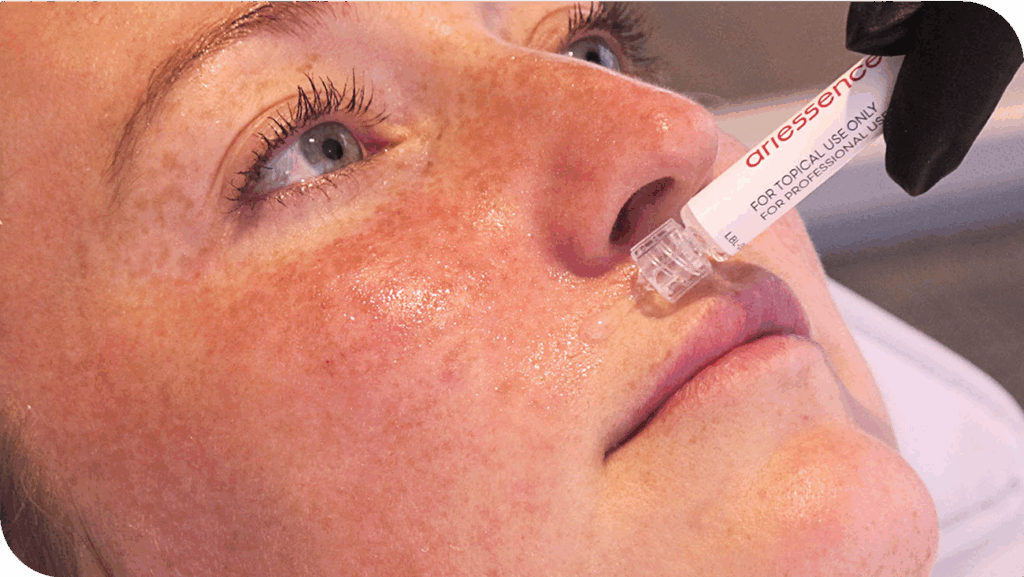

When used after treatments including microneedling, RF microneedling, laser skin resurfacing, and peels, ariessence pure PDGF+ can enhance your patient’s results and reduce downtime.

As a post-procedure topical application, ariessence pure PDGF+ is the ideal enhancement for a wide range of rejuvenative, aesthetic treatments.

ariessence applied post-microneedling